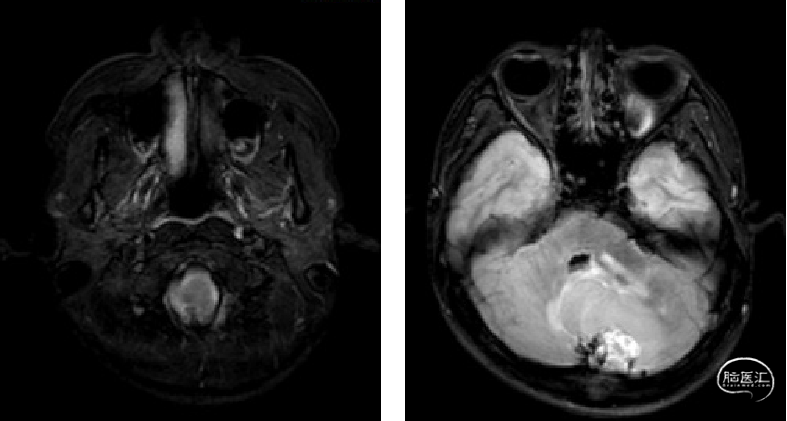

术前MRI

image.png

诊断及手术方式

术前诊断:

1.小脑、延髓占位(血管母细胞瘤)

2.梗阻性脑积水

手术方式:

枕下后正中入路延髓及小脑半球病损切除术